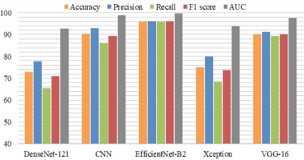

B. DenseNet121: DenseNet architectures are often denoted by the number of layers they contain. DenseNet-121 indicates a DenseNet with 121 layers, which is a common variant. When using DenseNet for a specific task, like image classification or medical diagnosis, the model is typically pre-trained on a large dataset and fine-tuned on the target task [23]. Their dense connectivity can lead to more efficient learning and better parameter utilization compared to traditional architectures [23]. The accuracy of DenseNet is about 71% because of which it cannot be used for this prediction model.

The figure 10 shows the workflow of how the comparative analysis has been carried out to select the best suited model for this case study.

C. EfficientNetB2: Algorithm—Efficient Net-B2 is trained for classification in the standard manner. EfficientNet-B2 is a specific variant of the EfficientNet family of neural network architectures [21]. Mingxing Tan and Quoc V. Le proposed the EfficientNet models in their paper “EfficientNet: Rethinking Model Scaling for Convolutional Neural Networks” in 2019. This model provides better performance and efficiency by depth scaling, width scaling, and resolution scaling of the network in a balanced way. EfficientNet is relatively consistent with near perfect training curves and provides less loss and Peak accuracy about 97.22%. figure.11 explains the modules of the EfficientNetB0.

D. Xception: The name “Xception’’ stands for “Extreme Inception,” indicating its relationship with the Inception architecture [20]. Depthwise separable convolutions have been utilized in the Xception which is one of the DL architectures [21]. Xception employs depthwise separable convolutions, which are a factorized version of the standard convolutional layers commonly used in convolutional neural networks (CNNs). Depthwise separable convolutions split the convolution into two stages. However, Xception uses a high number of parameters and computational cost is also high compared to other models. So Xcpetion cannot be used for this prediction model as it also provides less accuracy about 71.2%.

E. VGG16: VGG16 is created by the Visual Graphics Group [27]. When the pre-trained VGG16 model is used, it acts as a tool to extract important features from data, especially in imagerelated tasks. The top layers are removed (fully connected layers) from the VGG16 model, keeping the convolutional layers [23]. Add new layers on top of the VGG16 base to adapt it for AD classification [23]. Initialize the modified VGG16 model with pre-trained weights on a large dataset. Freeze the convolutional layers of VGG16 to retain the learned features and prevent them from being updated during initial training. The computational cost of VGG16 is comparatively less than other models used, but the loss rate is significantly high and provides an accuracy of about 88.02%.

F. Comparative analysis is done for the classification of AD to choose the best suited algorithm for better efficiency and accuracy. EfficinetNetB2 is the best suited method for the classification since it provides peak accuracy about 97.22% and also significantly less loss.

Performance evaluation metrics

Examining the model’s performance with respect to a certain dataset is a crucial task. This study assessed multiple evaluation metrics which includes recall, accuracy, precision, F1 score and area under the curve [7].